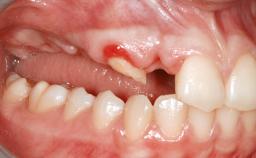

Shell Technique for Horizontal and Vertical Maxillary Bone Augmentation in a Partially Edentulous Patient with Aggressive Periodontal Disease

A 46-year-old woman was referred for treatment whose main complaints were mobility of her fixed partial dentures (right maxilla and left mandible) and periodontal bleeding during function. She also reported having taken systemic antibiotics to treat recurrent swelling in the area of the upper left molars. The patient had not seen a dentist for at least 2 years. She did not smoke and had no history of major systemic disease other than two minor orthopedic procedures some years back. The first-visit examination revealed poor plaque control, tooth mobility, periodontal disease, and a residual dentition widely associated with deep periodontal pockets.